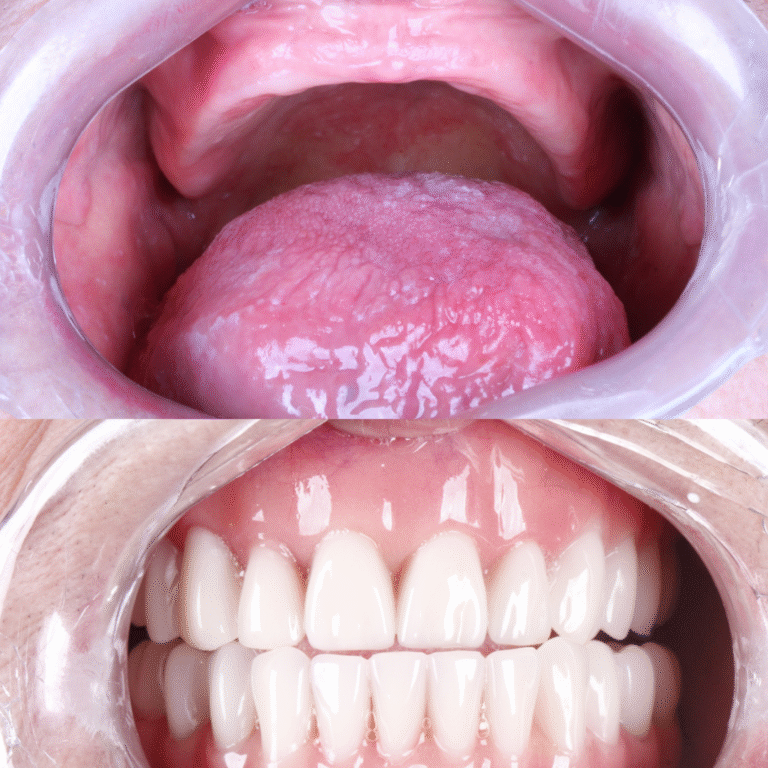

O All-on-Four é um protocolo de implantes dentários que utiliza apenas 4 implantes para fixar uma prótese total, substituindo todos os dentes da arcada.

Diferente de técnicas convencionais, não exige enxertos ósseos na maioria dos casos, tornando o tratamento mais rápido e confortável.

Em muitos casos, é possível instalar dentes fixos no mesmo dia da cirurgia. Isso significa que o paciente recupera a estética do sorriso e a função mastigatória muito mais rápido do que em técnicas convencionais.